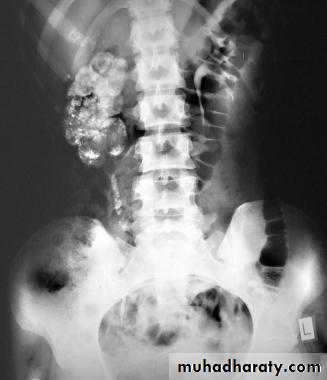

KUB

CALCULIMost renal stones are calcified and show varying density on plain x-ray films.

Pure uric acid & xanthine stones are radiolucent on plain radiography, but are well seen at CT or US.

Plain film is more sensitive than US for detecting ureteric calculi.

Stones regardless their composition are intensely echogenic (By U/S) and cast acoustic shadows